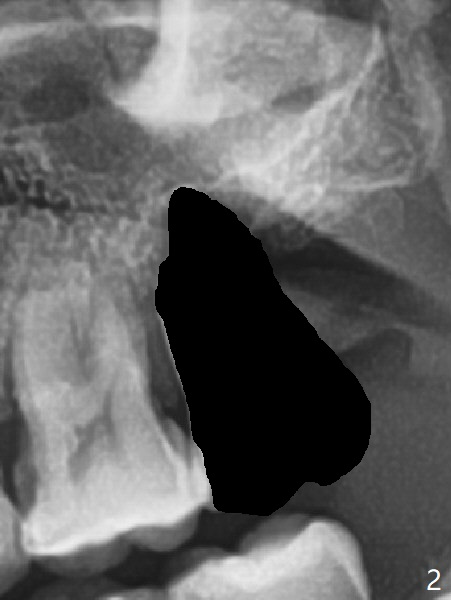

A 54-year-old man returns to clinic 5 months post SRP with chief complaint of UL loose tooth (#15, Fig.1). Since the remaining bone is limited after extraction, it is apparently unsuitable for immediate implant (Fig.2). Socket preservation seems to be able to gain bone height near gingival margin (Fig.3 red line). In fact 1 cc of cortical and cancellous bone mixture is used; after heavy debridement the bone graft is deposited on the distal root surface of the tooth #14 (Fig.4 arrow). The bone increases not only coronally, but also apically (Fig.5 blue lines, as compared to red lines denoting the original bone height). The bone reduces in height 10 months postop (Fig.6). Sinus lift is required for placement of a short implant (Fig.7). Socket preservation does not prevent post-extraction bone loss.